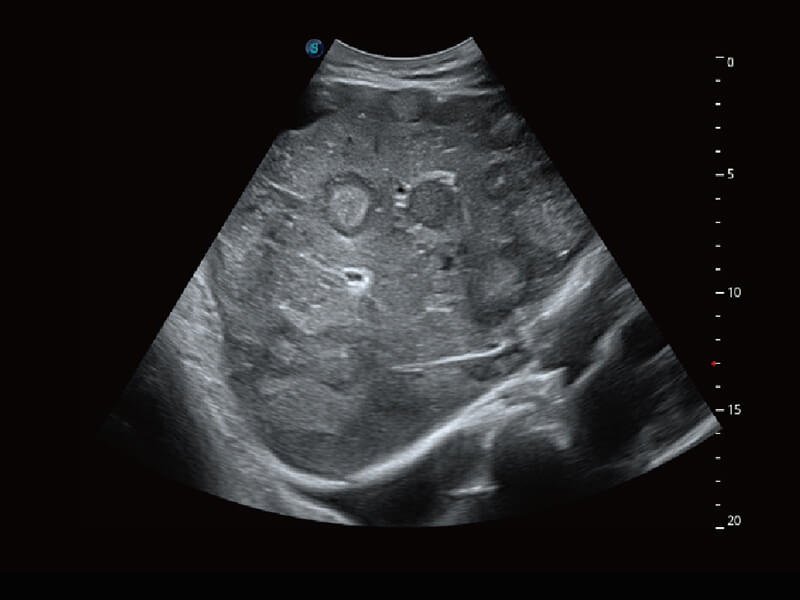

S60探头工艺,从前端信号处理每一个环节采集无损声学数据,真实还原组织原貌,再现解剖细节。

• 腹部单晶体探头( C1-6A )

临床图